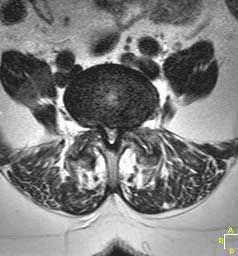

LUMBAR SPINAL STENOSIS, AXIAL VIEW.